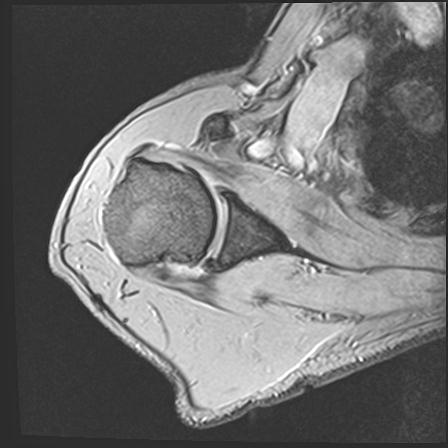

60058 3/9 11/4 右肩 2R+MRI 73歳男性 肩腱板損傷